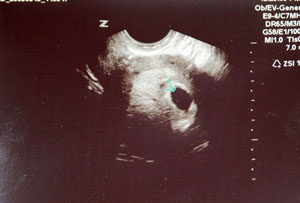

3. was ist denn mit deiner nichtvorhandenen mens, Yagu?? noch irgendwelche anzeichen fuer's eine oder andere??

10. ok, alles sieht prima aus. bin zurueck datiert worden von meinen eigenen berechnungen. bin heute 5+4 und auf US sah man die fruchthoehle und dottersack oder wie auch immer das heisst und in der anderen ecke der fruchthoehle lag der kronkruemel in seiner zellartigen masse. sie meinte alles sieht super aus und passt zur woche. denn ich gab ihr zwei empfaengnis daten und sie meinte es kann eigentlich nur der 18.4. sein denn demnach stimmt alles perfekt. also so weit alles supi. Riesengeroell purzelte vom herzen.